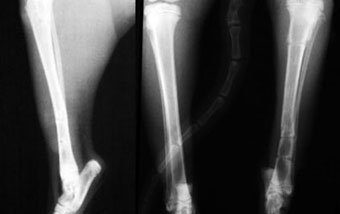

体重2.8kg、8か月齢の猫の上腕骨らせん骨折。

ピンニングと創外固定をタイインという方法で組み合わせることで、骨折部にメスを入れることなく整復固定しました。

写真上段: 手術前

写真中段: 手術直後